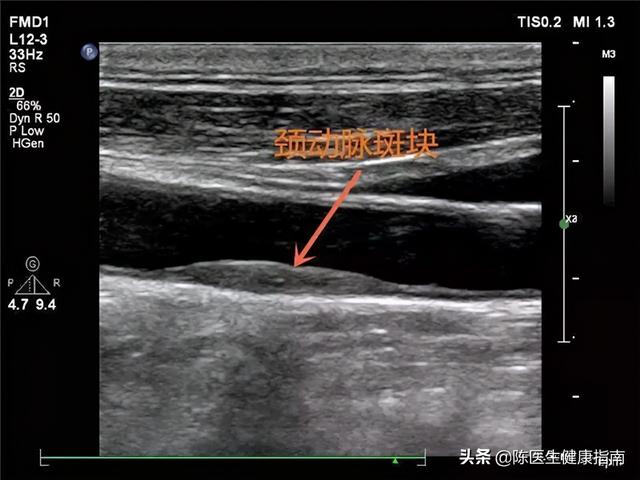

●颈动脉超声检查

动脉硬化和动脉硬化粥样都是由于血管病变,而导致各大动脉硬化,而颈部动脉属于人体大动脉之一,且连接肢体与头部血液流通及供应,位置独特、脂肪层较薄,因此若此处出现斑块,那么说明全身其他血管都有病变的可能。